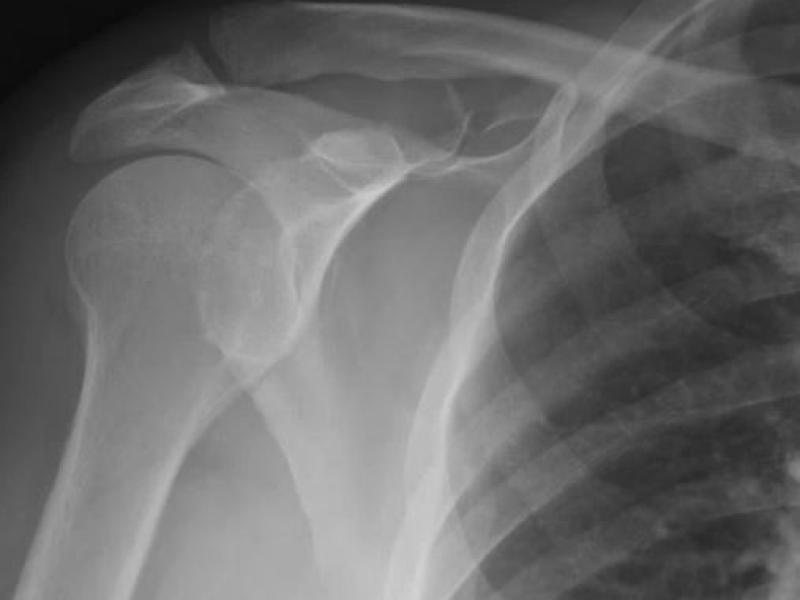

What's the Diagnosis? By Dr. Loran Hatch

EM Daily

December 22 2021

A 65 yo M presents to the ED after falling 10 feet off a